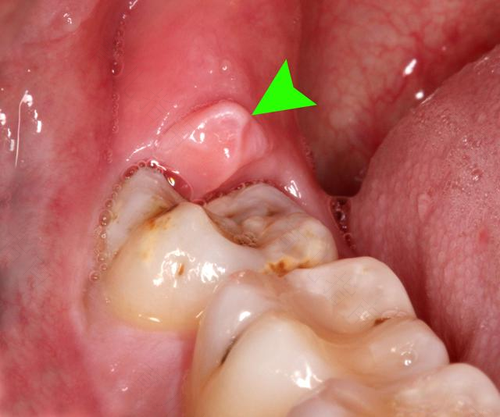

长智齿不分年龄大小,它长在牙齿的最里面,给大家的口腔健康带来了一定危害。由于它的生长会使别的牙太拥挤,就会引起牙疼,特别的疼,还会肿,连带的脸都肿的很高。那么长智齿了很疼怎么办?

长智齿有时也会引起发炎或牙龈肿痛,不要用舌头去添疼的地方,到了一定程度的时候会有脓流出来,可以用盐水来进行清洁,用淡盐水来涑口有很好的效果。在牙疼的时候,不要因为牙痛就不吃东西了,这样对自己的身体有影响的,容易造成营养不良。牙疼的厉害的时候,可以吃清火的食物,比如苦瓜,也可以吃喝一些营养汤,来补充营养。

牙疼是非常痛苦的,无论是什么原因导致的牙疼,最重要的就是保持口腔的清洁卫生。平时注意一下自己的饮食情况,不要吃的太辣,硬的东西也要少吃,尽量吃流食,减少牙的咀嚼,也不容易上火。脸部肿起来可以使用冰袋来敷敷脸,也可以改善牙齿的疼痛。还有一种方法,咬一片生姜也可以改善牙疼。如果牙齿疼,红肿的比较厉害,可以去医院让医生来解决,防止引起牙齿别的疾病。